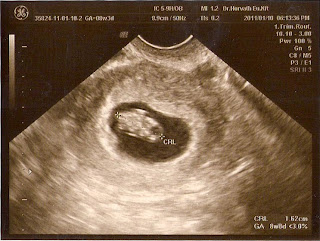

8.hét

Megjöttünk az orvostól, és minden a legnagyobb rendben volt. Épp koromnak megfelelő vagyok, és végre kis életjelet is adtam magamról szívem-lelkemet beleadva, anya nagy örömére.:) Jelenlegi születésem dátuma így 2011.08.22-re tehető, de ezt majd akkor úgyis elárulom. Anyát már két napja rosszullétekkel is nyúzom, biztos nagyon örül neki!:)